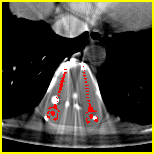

Visual comparison. As shown in Fig. 5, metallic implants such as spinal rods and hip prosthesis cause severe streaky artifacts and metal shadows, which obscure bone structures around them. cGan-CT cannot recover image intensity correctly for both cases. Sinogram domain or dual-domain methods perform much better than cGan-CT. LI, NMAR, and CNNMAR introduce strong secondary artifacts and distort the whole images. In NMAR images, there are fake bone structures around the metals, which is related to segmentation error in the prior image from strong metal artifacts. The segmentation error is also visible in NMAR sinogram. CNNMAR cannot restore the correct bone structures between rods in case 1. The tissues around the metals are over-smoothed in DuDoNet because LI sinogram and image are used as inputs, and the missing information cannot be inferred later. Our model retains more structural information than DuDoNet and generates anatomically more faithful artifact-reduced images.

Quantitative comparison. As shown in Table 2, we can see all the sinogram domain MAR algorithms outperform image enhancement approach cGAN-CT in PSNR and SSIM. It is because the sinogram restoration only happens inside the metal trace and the correct sinogram data outside the metal trace help to retain the anatomical structure. CNN-based methods (CNNMAR, DuDoNet, Ours) achieve much better performance than traditional methods, with higher PSNRs and SSIMs in image domain and lower MSEs in sinogram domain. Among all the state-of-the-art methods, CNNMAR achieves the best performance in sinogram enhancement and DuDoNet achieves the best performance in reconstructed images. The proposed method attains the best performance in all metal sizes, with an overall improvement of 4.2 dB in PSNR compared with DuDoNet and 99.4% reduction in MSE compared with CNNMAR.